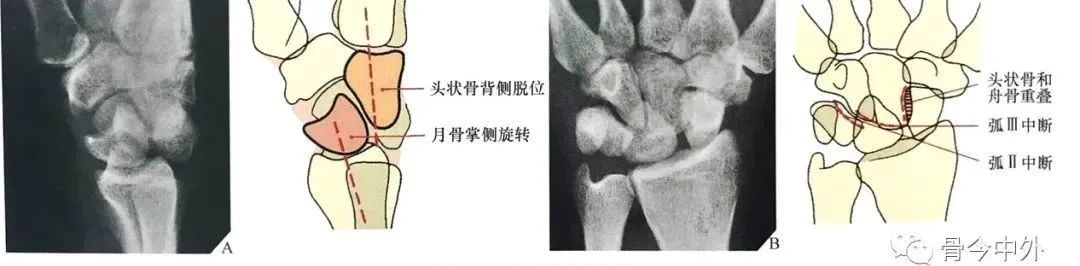

图21 左:月骨脱位;右:月骨周围脱位

月骨和月骨周围脱位:腕关节中立位置的背掌位和侧位X线片足以诊断月骨和月骨周围脱位。侧位像可以清晰显示在桡骨远端上方的月骨、头状骨和第三掌骨长轴呈直线状排列,这条线任何一点的中断都能确定半脱位或脱位的诊断。

当头状骨保持在直线上,一旦月骨成角度离开桡骨远端表面,月骨脱位即可被识别(图22A)。

同样的,在背掌位投照时,由舟骨远端凹面、月骨、三角骨所构成的弧线 II 的中断和相伴随的月骨三角形外观也可以诊断月骨脱位(图22B), 月骨脱位也能有效地从CT上显示,尤其是3D CT的重建图像(图23)。

图22 月骨脱位。(A)在腕关节侧位像上,月骨脱位时脱离由第三掌骨、头状骨和桡骨远端的长轴排列,月骨向掌侧旋转和移位。(B)背掌位投照显示弧线 II 在月骨位置中断。注意月骨的三角形外观及月骨脱位的征象。

在腕关节侧位片上,一旦头状骨长轴骨偏离月骨和桡骨远端表面所形成的直线而向背侧成角或掌侧成角,即可诊断月骨周围脱位。

月骨周围脱位时虽然月骨半脱位造成一定程度的月骨倾斜角,但月骨仍保留在与桡骨远端表面所形成的关节内(图24A)。

在背掌位片上,腕骨的近侧列和远侧列重叠、弧线 II 和弧线 Ⅲ 在头状骨的位置中断,提示月骨周围脱位(图24B)。

图24 月骨周围脱位。(A)腕关节侧位X线片显示典型的相对于月骨的头状骨背侧移位,虽然月骨轻度掌侧旋转,但仍保留在与桡骨远端所形成的关节内。注意第三掌骨、头状骨与月骨和桡骨远端所形成的直线中断。在背掌位投照X线片上(B),月骨周围脱位表现为由弧 II 和弧 Ⅲ 的中断所造成的腕骨近侧列与远侧列的重叠。